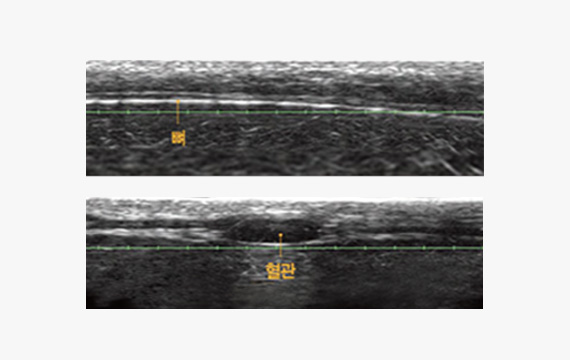

눈으로 보는 리프팅

실시간 DeepSEE™ 초음파 영상 기술로 시술 전 피부 두께와 조직층,

SMAS 위치를 직접 확인한 후 시술 깊이와 방향을 개인에 맞게 설정해

보다 안전하고 정확한 울쎄라피프라임 시술을 진행합니다.

울쎄라피프라임만의 DeepSEE™ 기술로 SMAS층까지 피부 속을 보고 개인에게 맞는 시술 계획을 세워

SEE

피부 속 조직층을

실시간으로 정확하게 확인합니다.